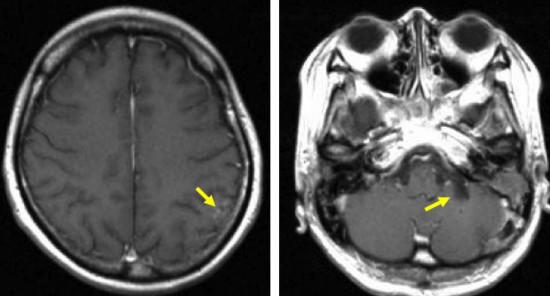

典型的な転移性脳腫瘍(単発)のMRI

腺癌の左前頭葉転移です。左のガドリニウム造影剤を使った画像では腫瘍が白く写っています。腫瘍の内部が一部壊死しているので黒っぽく見えます。右はフレア画像です。腫瘍の周囲の脳が腫れて脳浮腫(白く滲むようなところ)を生じています。

開頭手術で摘出した半年後の画像です。腫瘍は再発していなくて,脳の腫れも引いています。転移が発見された時には,見当識障害などの左前頭葉症状が強かったし,摘出がとても簡単な場所だったので手術しました。線状皮膚切開・小開頭ですから1時間くらいの簡単な手術です。でも,26mmくらいでしたから,定位放射線治療も可能なものでした。この患者さんは幸いなことに半年で再発していませんが,開頭手術による摘出だけだと同じ場所からまた再発することもあり,それから放射線治療を加えなくてはならないこともあります。個々の判断は難しいのですが,基本的には開頭手術より定位放射線治療のほうがいいと考えて下さい。